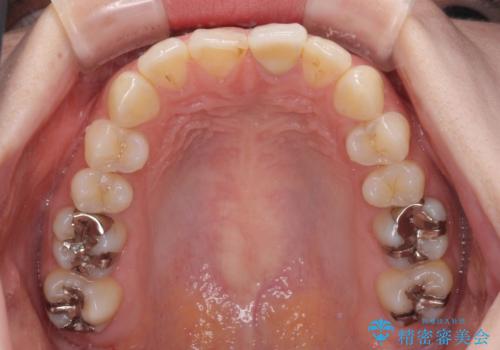

前歯1歯でのオールセラミッククラウンでは、オーダーメイドタイプのクラウンを選択していただき、周辺の歯と色調を合わせるようにするのですが、今回は既製タイプを選択されました。